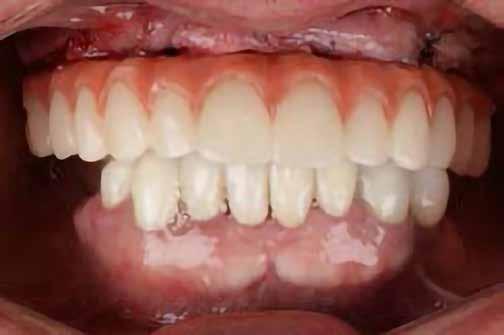

A 2020 januárjában elkezdett kezeléssorozat befejezését az év márciusában, hazánkba is begyűrűző Covid-19 pandémia késleltette, így kb. 6 hónap gyógyulás után láttunk hozzá az emergencia profil és a gingivális zenit ideiglenes koronával történő formázásához (11. és 12. kép). A 3 hetente végzett apró alakításokkal sikerült megfelelő ínyprofilt kialakítani, a „rózsaszín esztétika” a páciens számára is megfelelő volt. A bal felső nagymetsző fog meziális kompozit tömés cseréjét követően, individualizált nyitott kanalas lenyomati fejet készítettünk: az akrilát ideiglenes korona profilját átlátszó szilikonnal lemásoltuk, majd a körszimmetrikus gyári lenyomati fej és az ideiglenes korona kontúrja közötti hézagot folyékony kompozittal töltöttük ki (13. kép). Az így készített egyéni lenyomati fejjel vettünk lenyomatot a végleges, kerámialeplezésű cirkónium-dioxid vázas, átmenő csavaros rögzítésű koronához. (A fogtechnikai munkát Nébl Péter fogtechnikusmester készítette.), (14., 15., 16 és 17. képek).

A kész korona átadásakor a páciens elégedett volt az esztétikával, az azóta eltelt évben rendszeres kontrollokon jelent meg, melyek során meggyőződtünk a kemény- és lágyszövetek stabilitásáról (18. és 19. képek).

17. a–b képek: A kész munka átadáskor. 18. a–c képek: 1 éves kontroll. 19. kép: Intraorális kontroll röntgen felvétele 1 évvel az átadás után.